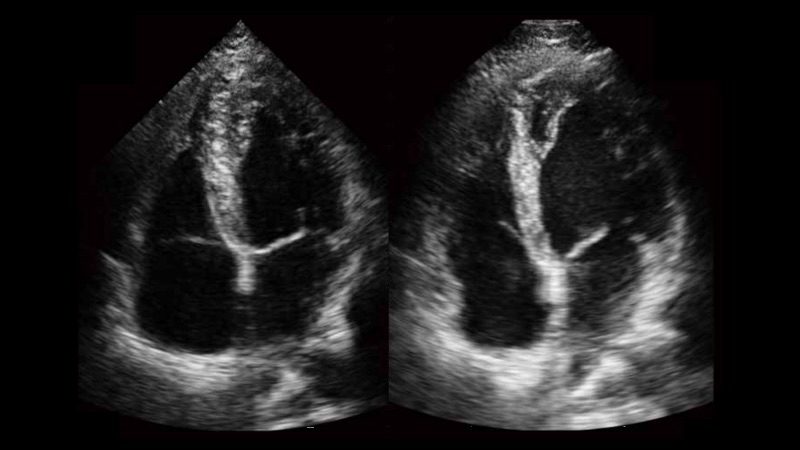

• 心内膜自动描迹Auto EF

自动识别收缩和舒张末期心肌内膜,自动计算射血分数EF值。